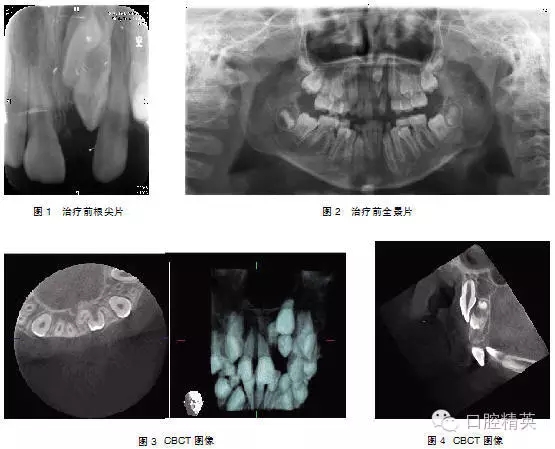

典型病例3:患者,男,11岁,因—1未萌来我院就诊(图1)。

检查: |1未萌,1|全萌,1|2之间间隙为5mm。X线片示: |1骨内埋伏,倒置,埋伏牙倒置角度在130°,牙冠的腭侧面向外,稍弯根,1| 牙根基本形成(图2~4)。

处理:行外科开窗+正畸牵引治疗,6个月后破龈萌出,连续牵引,12个月后到位(图5~7)。